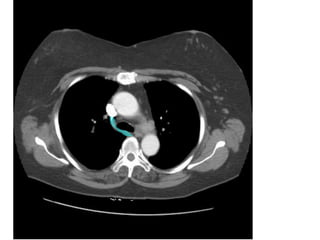

VỠ LOÉT ĐỘNG MẠCH CHỦ NGỰC

-> MÁU XOANG NGỰC (T)

VỠ LOÉT ĐỘNGMẠCH CHỦ NGỰC -> MÁU XOANG NGỰC (T)